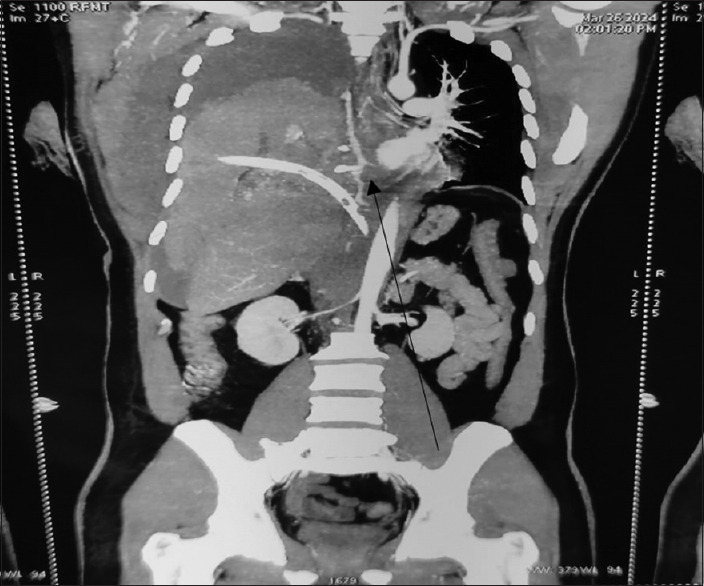

肋间动脉瘤是一种血管异常,具有潜在的破裂风险,可能导致危及生命的血胸。本病例报告介绍一位年轻男性,他经历了肋间动脉瘤破裂,随后在剧烈运动后出现大量血胸。目前的病例研究揭示了在周边环境下处理此类病例的困难和经验教训,包括是否插入肋间胸引流管(ICD)的困境。患者最终被诊断为一种罕见的临床症状,即右侧后肋间动脉瘤破裂伴大量血胸。

Abstract: Intercostal artery aneurysms are a type of vascular abnormality that poses a potential risk of rupture, which could lead to life-threatening hemothorax. This case report presents a young male who experienced a rupture of an intercostal artery aneurysm and subsequently suffered from a massive hemothorax after engaging in strenuous physical activity. The current case study sheds light on the difficulties and lessons learned in managing such cases in peripheral settings, including the dilemma of whether to insert an intercostal chest drain (ICD). The patient was ultimately diagnosed with a rare clinical entity known as rupture of right posterior intercostal artery aneurysm with massive hemothorax.